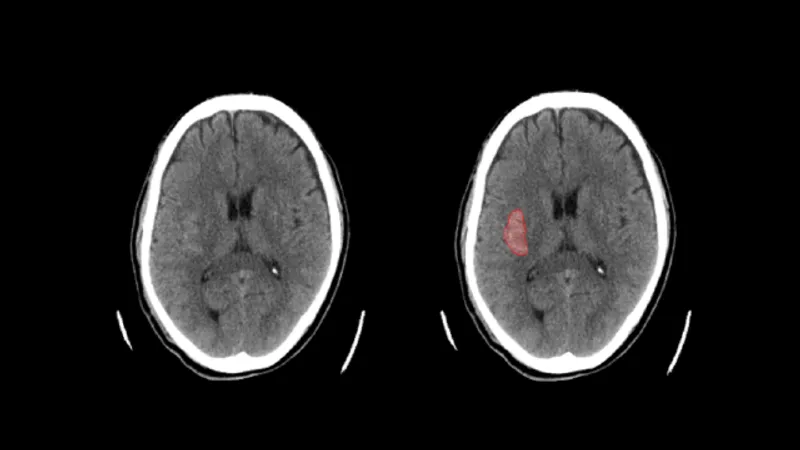

頭部CT画像から 高吸収/低吸収領域及び組織構造・境界の不明瞭化がみられる領域の抽出

頭部単純 CT 画像情報から高吸収・低吸収領域、組織構造・境界の不明瞭化領域の抽出を行います。

頭部単純 CT 画像の画像情報から、画像に基づく画素値の分析を行い、以下の情報を提供します。 (1) 頭蓋内で周囲及び前後のスライスと比べ高吸収の領域 (2) 頭蓋内で周囲及び前後のスライスと比べ低吸収の領域 (3) 頭蓋内で前後のスライス及び同一スライス内の左右で比較して組織構造もしくは組織境界